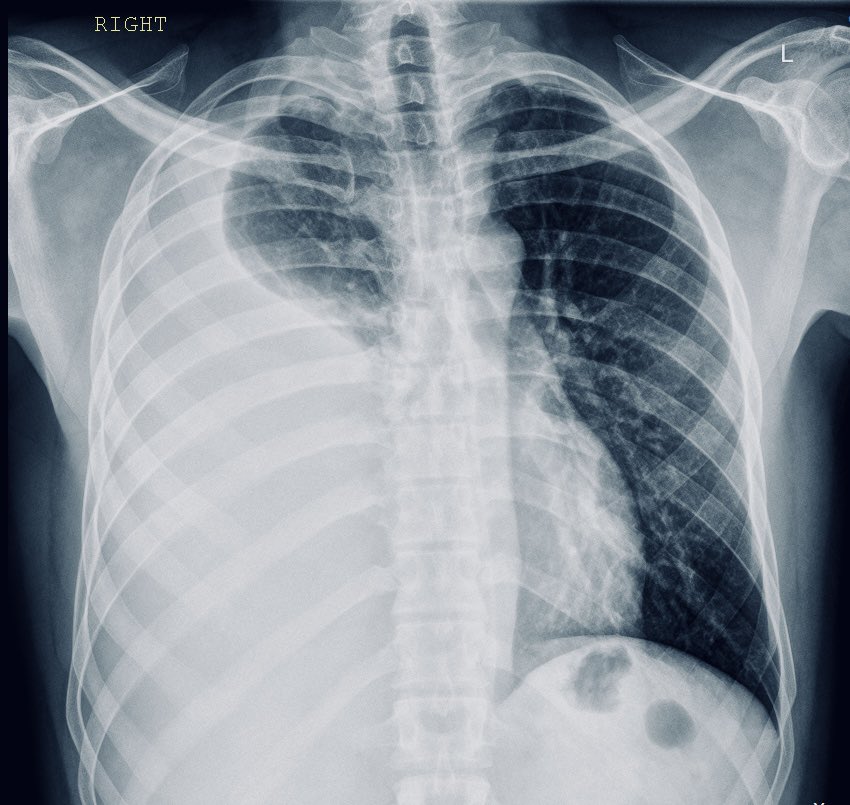

DocXus Right-sided Pleural Effusion โž” Blunted right costophrenic angle โž” Meniscus sign (concave line) at right lung base โž” indicates fluid accumulation โž” Increased density in right lower lung fields โž” suggests right-sided pleural effusion

<a href="/docxusofficial/">DocXus</a> Right-sided Pleural Effusion

โž” Blunted right costophrenic angle

โž” Meniscus sign (concave line) at right lung base โž” indicates fluid accumulation

โž” Increased density in right lower lung fields โž” suggests right-sided pleural effusion